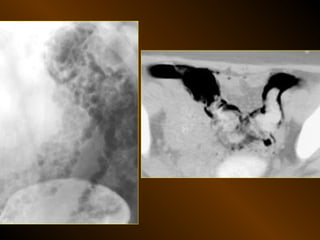

KHÍ TỰ DO

TRONG KHOANG PHÚC MẠC

NGUYÊN NHÂN

thủng tạng rỗng

nguồn gốc xuyên phúc mạc

nguồn gốc trong phúc mạc

10 – 15% thủng tạng rỗng → không thấy hơi tự do ổ bụng

TỤ KHÍ NGOÀI PHÚC MẠC

• Nguyên nhân :

– Thủng tạng rỗng

– Áp xe tạo khí

• X quang quy ước

• Siêu âm

• XQCLĐT

KHÍ TỰ DO TRONGKHOANG PHÚC MẠC NGUYÊN NHÂN thủng tạng rỗng nguồn gốc xuyên phúc mạc nguồn gốc trong phúc mạc 10 – 15% thủng tạng rỗng → không thấy hơi tự do ổ bụng

TỤ KHÍ NGOÀIPHÚC MẠC • Nguyên nhân : – Thủng tạng rỗng – Áp xe tạo khí • X quang quy ước • Siêu âm • XQCLĐT